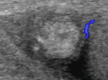

Scrotal trauma accounts for less than 1% of all trauma-related injuries. Traumatic injuries of the epididymis are extremely rare.Here we report a rare case of hematoma of the epididymis, diagnosed with US, in a 10-year-old boy after a sport injury.